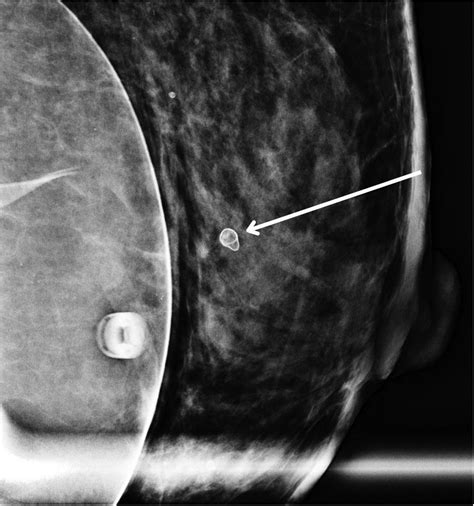

• Imaging Tests: Imaging tests such as mammography, ultrasound, or MRI may be used to visualize the affected tissue and rule out other conditions.